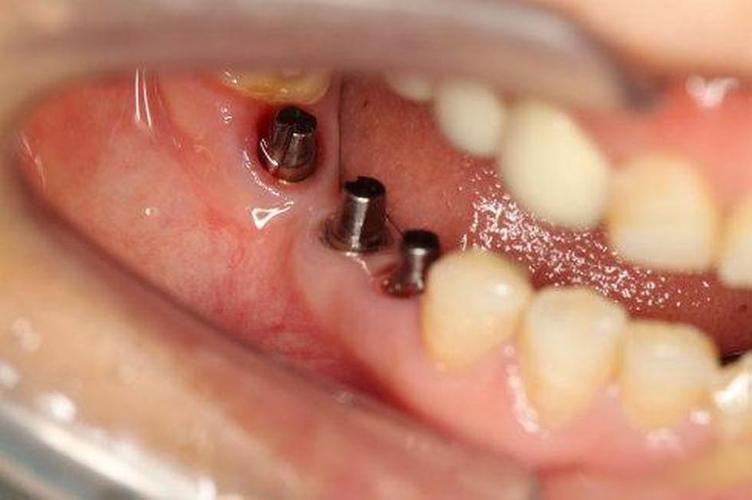

医生会通过口腔检查缺牙区牙龈、邻牙情况,并借助CBCT(锥形束CT)精确测量牙槽骨的高度、宽度、密度,以及神经管、上颌窦等重要结构的位置,判断是否具备直接种植条件,或需植骨、上颌窦提升等辅助手术。

(图片来源网络,侵删) -

骨条件满足后,即可进行种植体植入手术,医生会在局部麻醉下,逐级备洞后将种植体(纯钛或钛合金材质)植入牙槽骨内,缝合伤口,种植体植入后需等待3-6个月(上颌骨可能需4-6个月,下颌骨需3-4个月),期间种植体与牙槽骨形成牢固的骨结合,这是种植牙成功的关键。

基台安装与牙冠修复